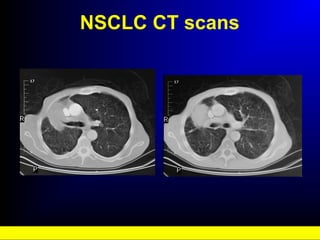

NSCLC CT scans

• #21 Non-small cell lung cancer CT scans: There is a mass measuring approximately 5cm x 5cm. Tiny lung metastases are also evident on the images. Computerised tomography scanning provides a more accurate location of the tumour than the X-ray; it is, therefore, valuable if surgery or radiotherapy is contemplated. CT scans can detect chest wall invasion and mediastinal lymphadenopathy, either of which are contraindications to surgical resection. Inclusion of the liver and adrenal glands can also detect distant metastasis in these organs. Some studies have shown that low dose spiral CT in comparison with conventional radiography of the chest was superior for screening and detection of small peripheral lung cancers.1 However, a much larger-scale clinical trial is warranted to further examine this.1 1.Kaneko M, et al. Radiol 1996; 201: 798 - 802 1. Webb WR, et al. Radiology 1991; 178: 705-713.